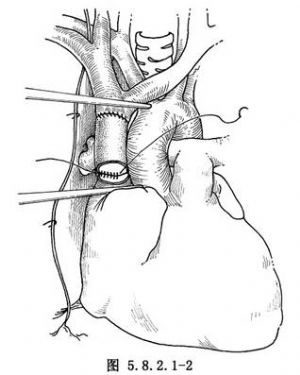

5.切除上腔靜脈前,先解剖和遊離阻塞段上腔靜脈的近心端(上腔-右房接合點)和遠心端(左、右無名靜脈的匯合處),然後各置一把Potts鉗(圖5.8.2.1-1)。

6.上腔靜脈切除後,用18或20號的聚四氟乙烯(PTFE)人造血管與上腔靜脈吻合。先吻合遠心端,用5-0的Prolene線,在上腔靜脈的遠端和人造血管之間縫兩條牽引線,結紮後用連續外翻縫合法,分別縫合前、後壁,打結在血管外面。同樣的方式,吻合近心端(圖5.8.2.1-2)。近心端縫線未打結前,向移置血管內注入肝素鹽水沖洗,然後放開遠端Potts鉗,排淨移置血管內所有空氣,最後移去近端阻斷鉗(圖5.8.2.1-3)。